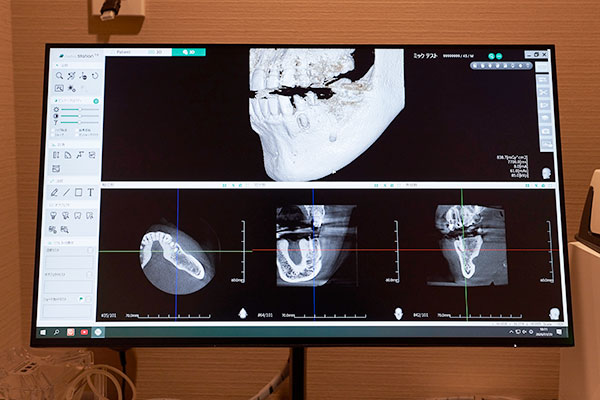

安全なオペを行うためには、目に見えない骨の内部構造を正確に把握することが不可欠です。 当院では、歯科用CTを用いた精密検査を実施しています。CTによる多角的な診断で、骨の厚みや密度、神経・血管の位置を詳細に把握。さらに、そのデータを活用してコンピューター上で埋入シミュレーションを行い、インプラントの配置(位置・角度・深さ)を決定します。事前にリスクを徹底的に排除し、医学的根拠に基づいた安全な治療計画を立案します。